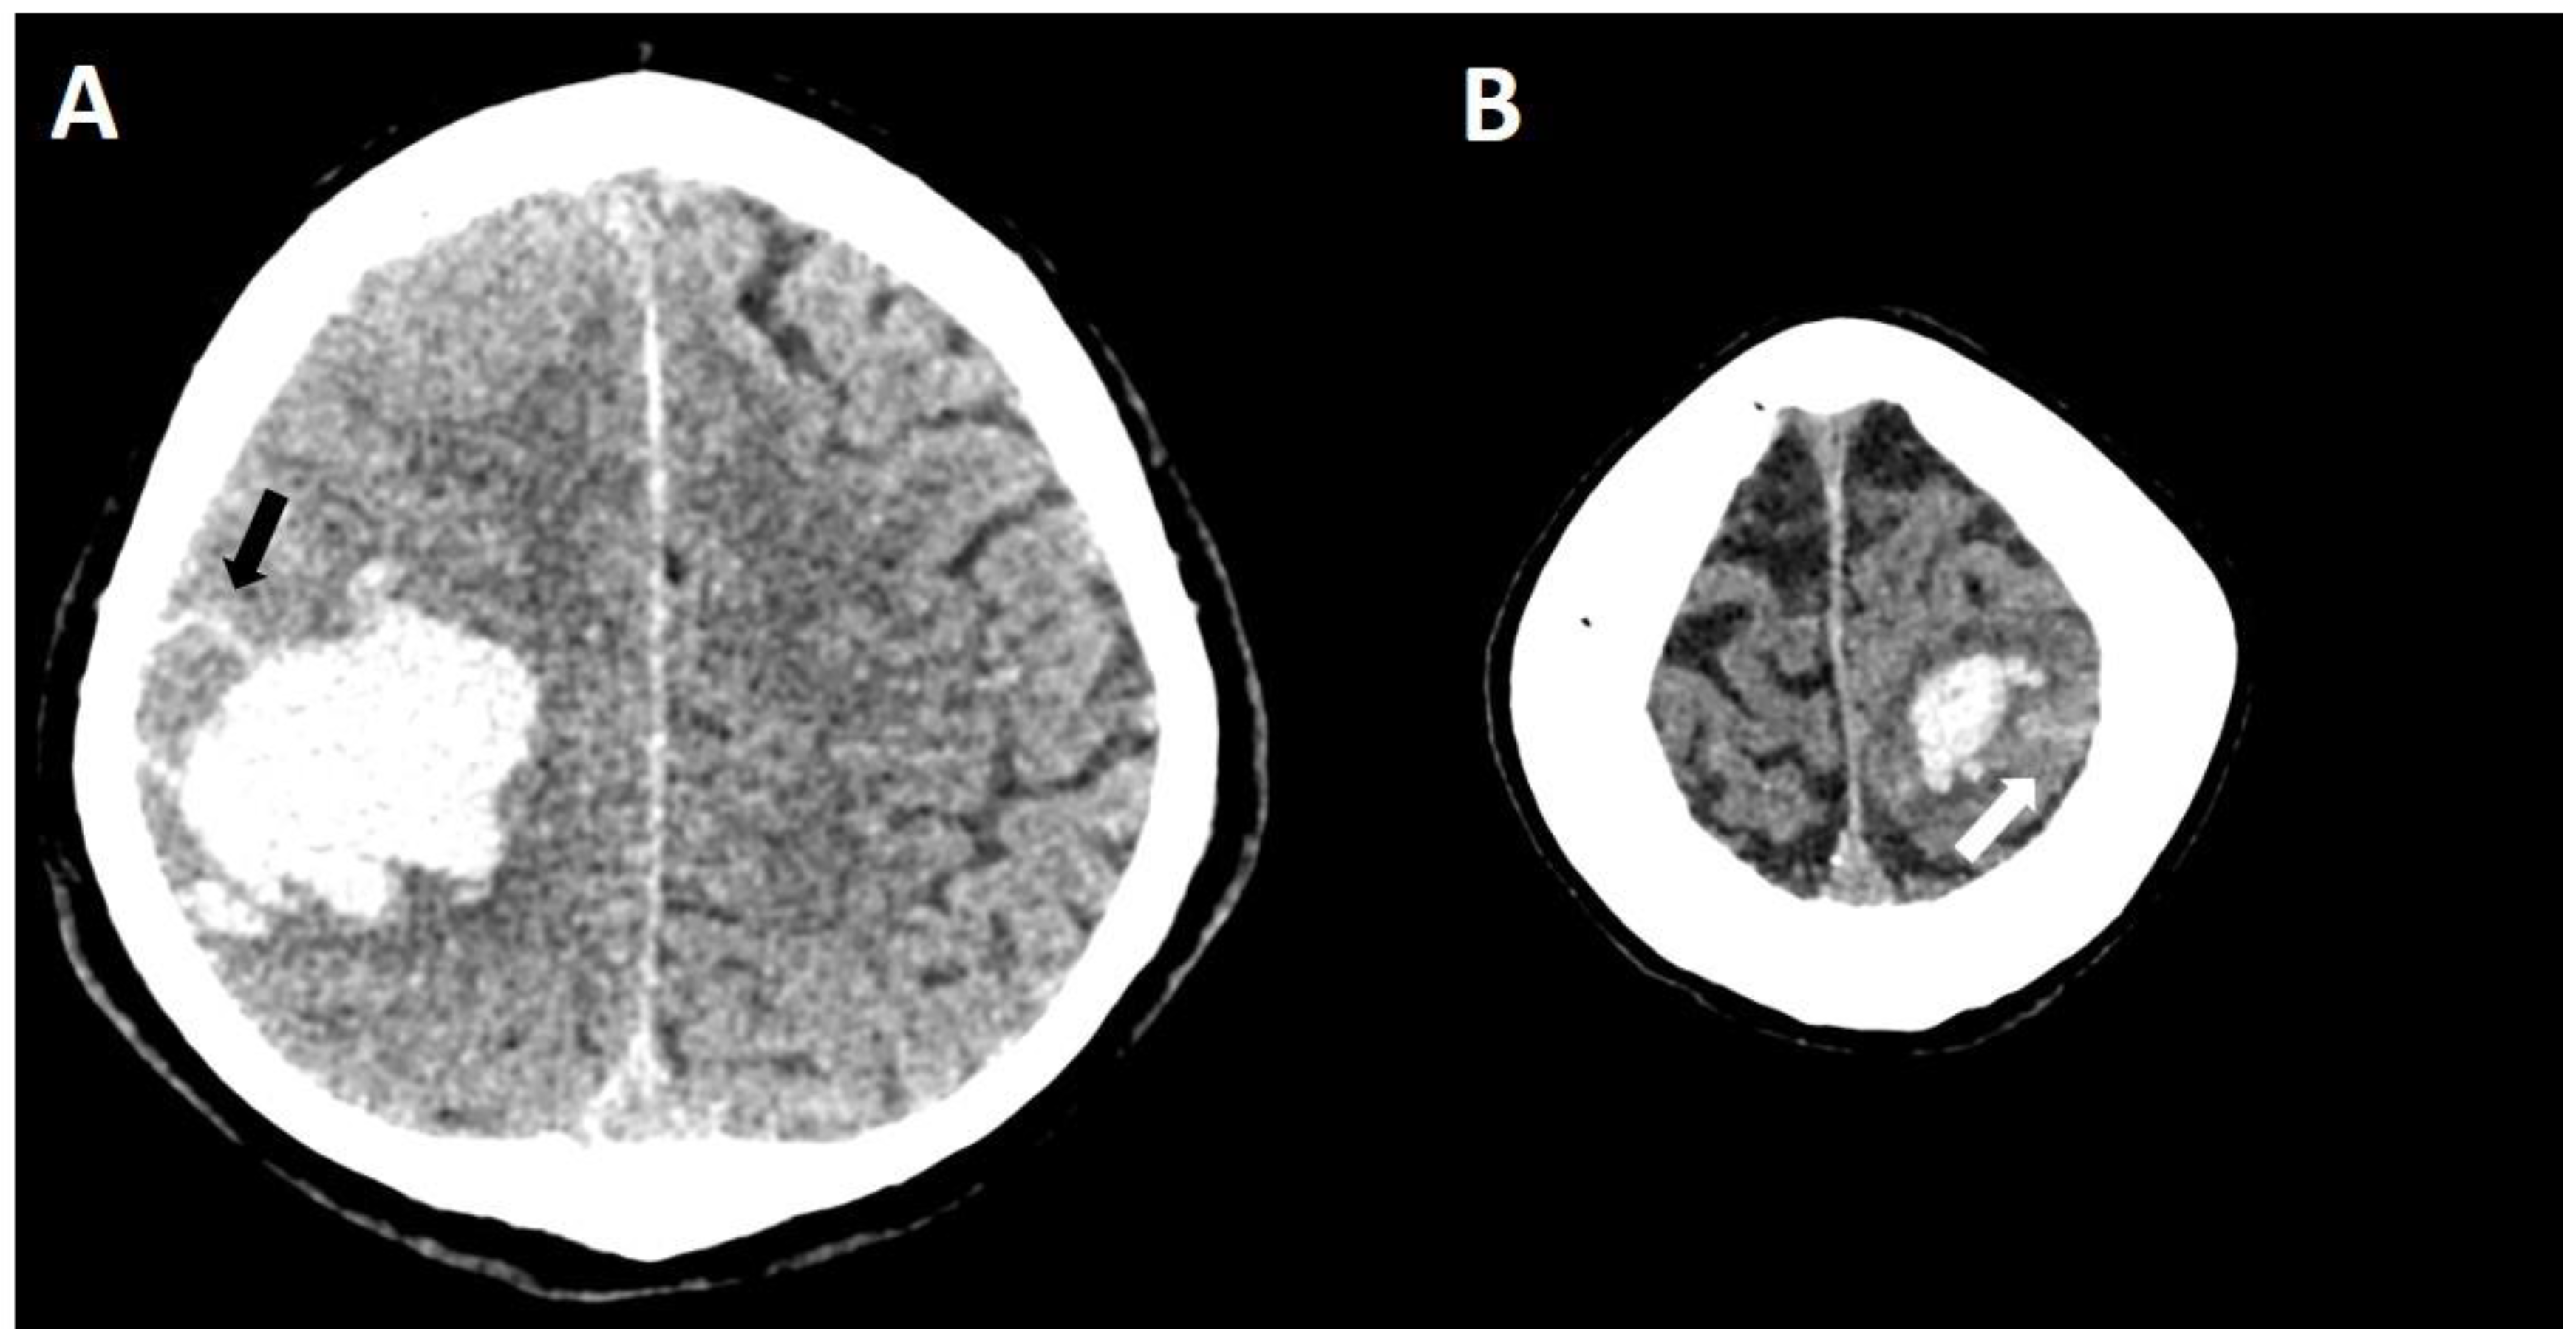

5.1.1. Lobar Hemorrhages

5.1.2. Multiple Cerebral Microbleeds

5.1.3. Convexity Subarachnoid Hemorrhage